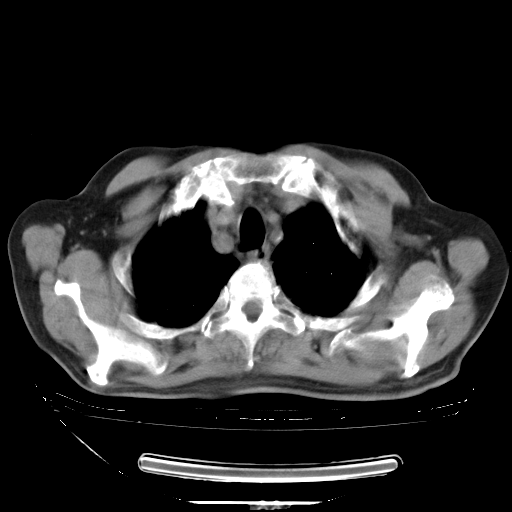

今天复查肺部CT,发现双肺广泛磨玻璃样改变。所以我把3月19日和5月9日相隔50天的肺部CT上传。请大家会诊。

2009年3月19日肺部CT片。

5月9日肺部CT(在4月27日齐鲁医院肺部CT描述部分肺组织磨玻璃样改变,12天后肺组织广泛磨玻璃样改变)